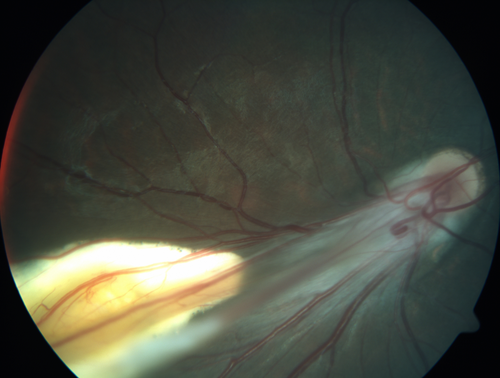

Familial Exudative Vitreoretinopathy - FEVR - Stage 4b OD

10 year old child with poor vision OD from birth.  The left eye had vascular remodelling in the temporal periphery with preretinal abnormalitlies seen on OCT.  The patient never returned for a fluorescein angiogram.  Left eye is either stage 1 or stage 2. no family history